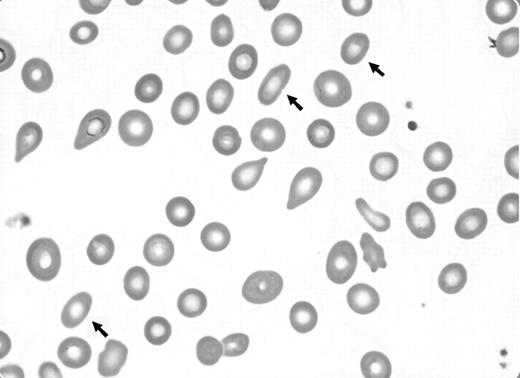

We wish to comment on the recent Blood Work image titled “Dacryocytes (teardrop cells).”1 The San Diego Hematopathology Club recently had a discussion of dacryocytes. It was pointed out by one of the senior members of the group that dacryocytes are invariably accompanied by an additional abnormal erythrocyte that is best characterized as a stubby elliptocyte. Further, in numerous published images of dacryocytes,2 (p 235), 3 (p 187), 4 (p 1300), 5 (p 566) at least one such cell is present but almost never mentioned. Dr Maslak's image1 supports this assertion (see arrows in Figure 1).

We informally tested the assertion that elliptocyte-like cells are a ubiquitous feature of leukoerythroblastosis. Peripheral blood films were evaluated from 30 archived cases with leukoerythroblastosis, predominantly from patients with primary myelofibrosis, for the presence of dacryocytes and stubby elliptocytes. The latter cell type, defined as an erythrocyte with 2 parallel membranes and a length to width ratio of between 1.5 and 2. 5 to 1, outnumbered dacryocytes on average more than 3 to 1. These cells were present in every examined peripheral blood film. As well, the relative proportions of stubby elliptocytes and dacryocytes remain relatively constant in cases as the leukoerythroblastic changes become more prominent.

The dacryocyte is appropriately recognized as the hallmark poikilocyte of leukoerythroblastosis. However, there is a dearth of references that have emphasized the constant presence of elliptocyte-like cells in this setting. This cell type certainly lacks the diagnostic specificity of dacryocytes, and stubby elliptocytes are present in other hematologic disorders. Stubby elliptocytes are present in iron deficiency, thalassemias, and other hereditary erythrocyte abnormalities, although they are not a dominant finding in these settings. Nevertheless, the identification of stubby elliptocytes, particularly in the clinical setting of suspected myeloproliferative disease, should prompt a diligent search for subtle but more definitive evidence of leukoerythroblastosis which has particular utility in the distinction between the cellular phase of primary myelofibrosis and essential thrombocythemia.